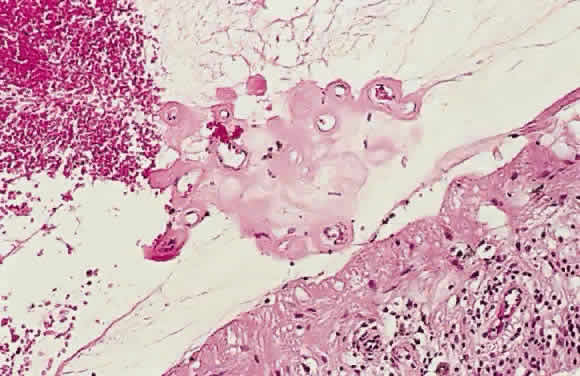

Fig. 17. A. A histologic section stained with H & E demonstrating vascularized

membranes on the disc and retina. Tractional retinal detachment is present. Notice

the subretinal fluid (amorphous eosinophilic material). B. Fundus photograph of fibrous tissue emanating from the disc in patient

with proliferative diabetic retinopathy. The disc is pale; the macula

is edematous with exudate. Pigmented laser spots are visible temporally. Fig. 17. A. A histologic section stained with H & E demonstrating vascularized

membranes on the disc and retina. Tractional retinal detachment is present. Notice

the subretinal fluid (amorphous eosinophilic material). B. Fundus photograph of fibrous tissue emanating from the disc in patient

with proliferative diabetic retinopathy. The disc is pale; the macula

is edematous with exudate. Pigmented laser spots are visible temporally.

|